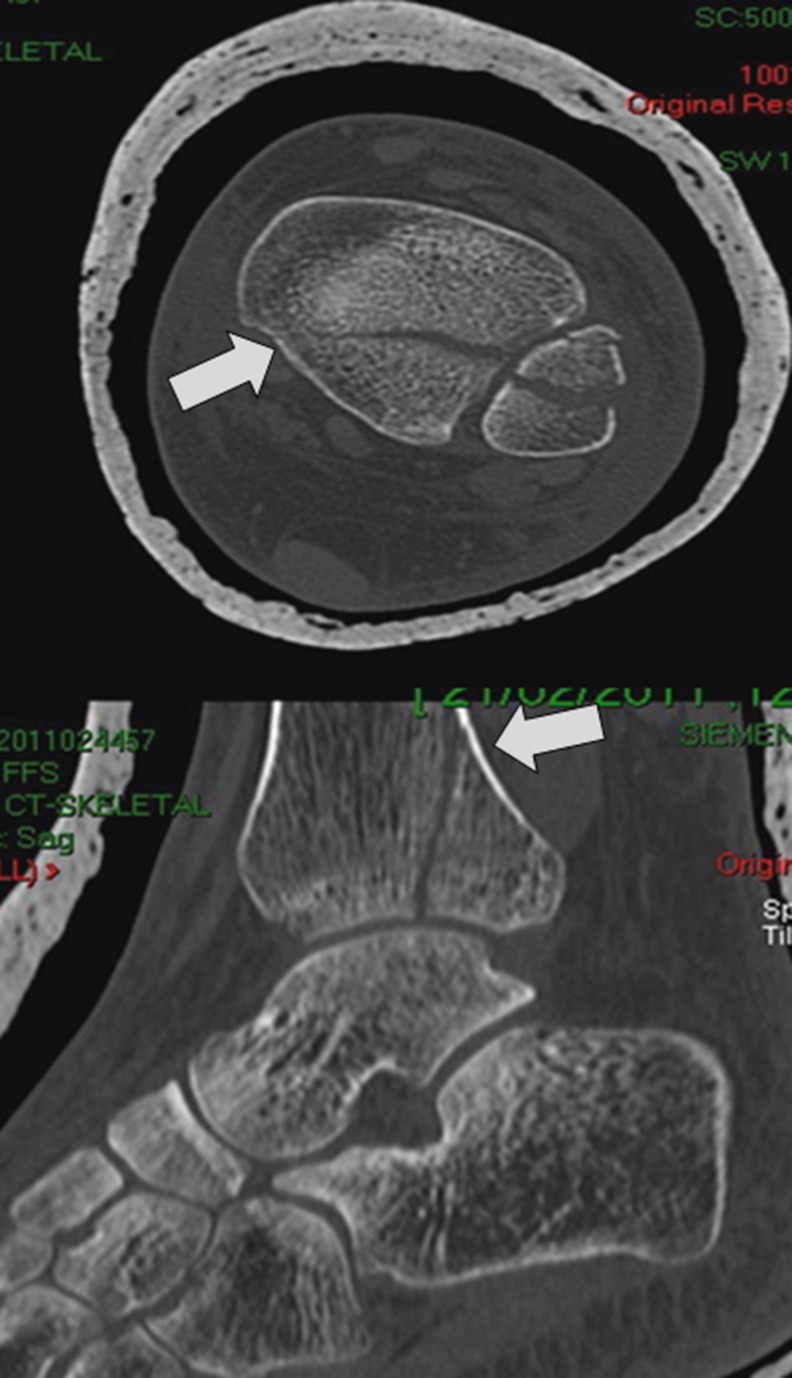

Fig. 3.

Axial and sagittal computed tomography (CT) cuts of the same case presented in Fig. 1 disclosing a concomitant posterolateral oblique-type fracture of the posterior malleolus

A questionnaire-based study was conducted among surgeons attending the 2012 European Federation of National Associations of Orthopaedics and Traumatology Conference (EFORT) in Berlin, Germany. Participants were asked to complete a questionnaire (Fig. 1) regarding their treatment preferences for minimally displaced lateral malleolus fractures as seen on standard non-weight-bearing trauma series radiographs (Fig. 2). The same questionnaire was then presented to the participants with the addition to the case of sagittal and axial computed tomography (CT) images that disclosed a concomitant minimally displaced posterolateral oblique-type fracture of the posterior malleolus involving between 30 % and 50 % of the articular surface (Fig. 3). Type of subspecialty, type of practice (academic university-affiliated, nonacademic), number of years in practice, and volume of trauma surgery were also provided by each participant.